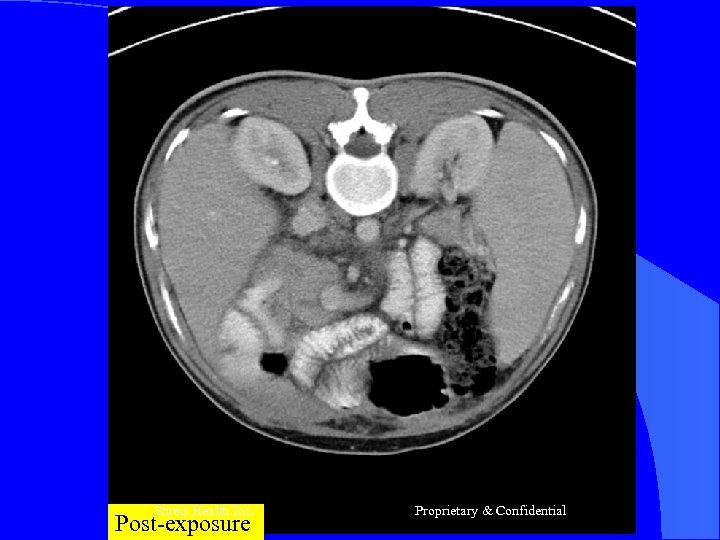

CASE 4 l l l Mr D, 44 yrs Sept 2003 -SOJ (Se Bil=4. 5, Alk. PO 4=450 BX of pre-op lesion = PD Adeno Ca Nov 2003 -Op n-Inoperable mass head pancreas (1”) -Infiltrating SMR/PV =>Palliative-C cys J +GJ Chemo – gemcit 5# Presentation – Cachexic - Wt loss 20 Kg Shreis Health Inc. Proprietary & Confidential

RFQMR-1# 01 Jan – 31 Jan 2005 -2# 15 Feb – 28 Feb 2005 CT scans – Sept 2003 – Jan 2005 = Progress of Lesion Jan 2005 – Sept 2005 = static Went back to Duty- April 05 Shreis Health Inc. Proprietary & Confidential

Shreis Health Pre-exposure Inc. Proprietary & Confidential

Shreis Health Inc. Post-exposure Proprietary & Confidential